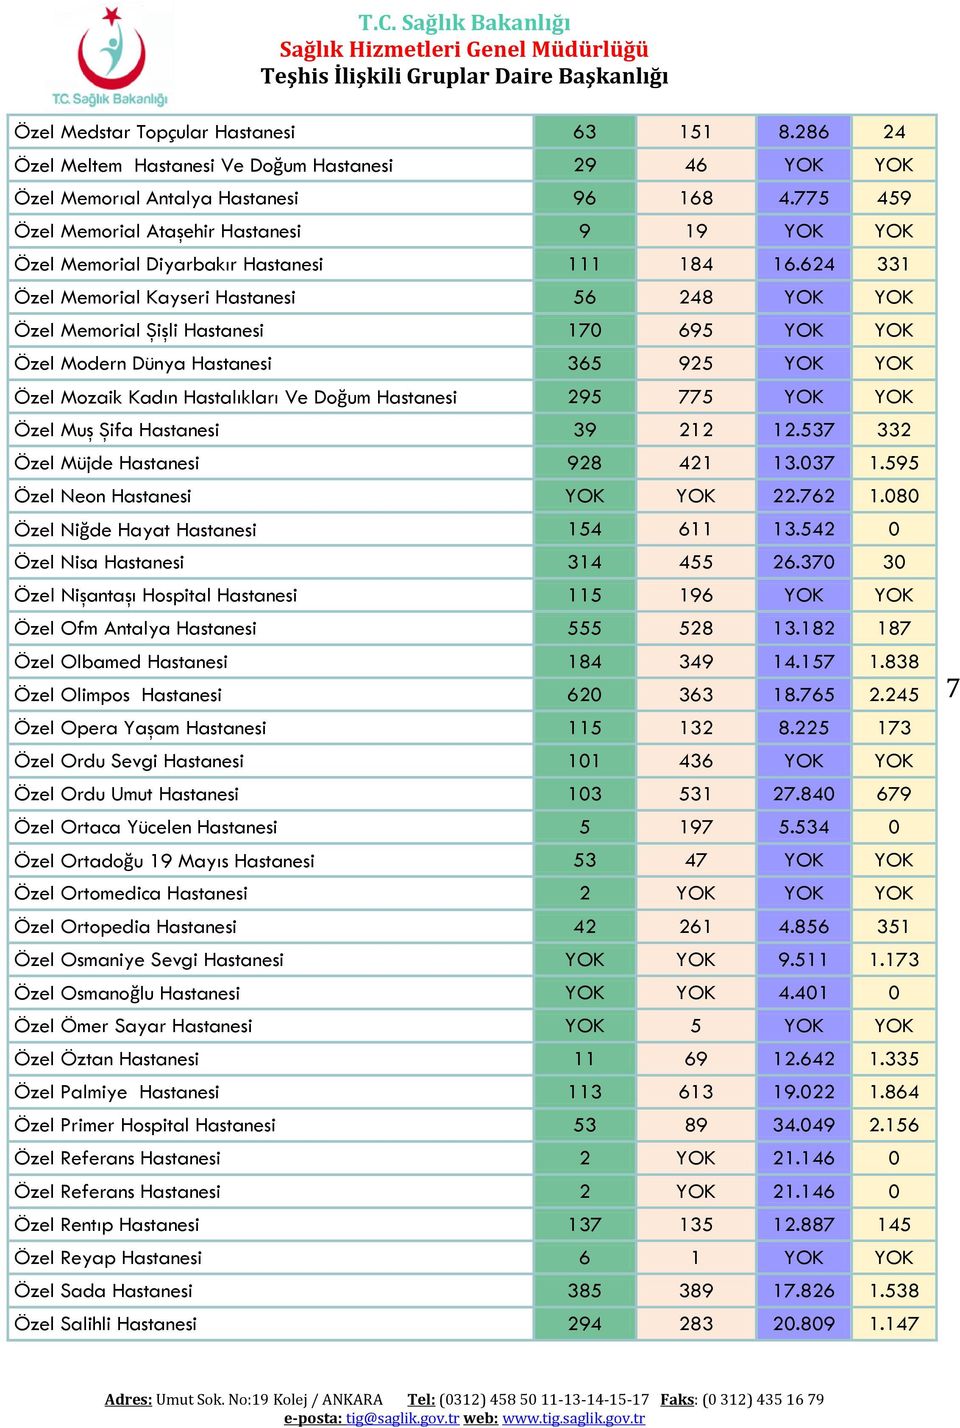

T C Saglik Bakanligi Saglik Hizmetleri Genel Mudurlugu Teshis Iliskili Gruplar Daire Baskanligi Pdf Free Download